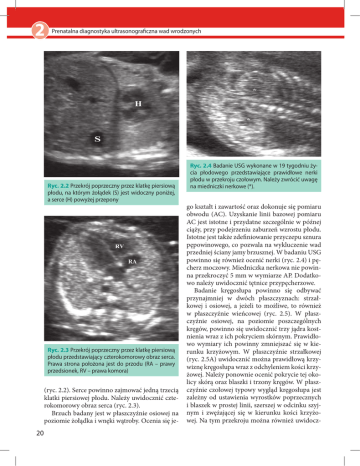

2 Prenatalna diagnostyka ultrasonograficzna wad wrodzonych Ryc. 2.2 Przekrój poprzeczny przez klatkę piersiową płodu, na którym żołądek (S) jest widoczny poniżej, a serce (H) powyżej przepony Ryc. 2.3 Przekrój poprzeczny przez klatkę piersiową płodu przedstawiający czterokomorowy obraz serca. Prawa strona położona jest do przodu (RA – prawy przedsionek, RV – prawa komora) (ryc. 2.2). Serce powinno zajmować jedną trzecią klatki piersiowej płodu. Należy uwidocznić czterokomorowy obraz serca (ryc. 2.3). Brzuch badany jest w płaszczyźnie osiowej na poziomie żołądka i wnęki wątroby. Ocenia się je- 20 Ryc. 2.4 Badanie USG wykonane w 19 tygodniu życia płodowego przedstawiające prawidłowe nerki płodu w przekroju czołowym. Należy zwrócić uwagę na miedniczki nerkowe (*). go kształt i zawartość oraz dokonuje się pomiaru obwodu (AC). Uzyskanie linii bazowej pomiaru AC jest istotne i przydatne szczególnie w późnej ciąży, przy podejrzeniu zaburzeń wzrostu płodu. Istotne jest także zdefiniowanie przyczepu sznura pępowinowego, co pozwala na wykluczenie wad przedniej ściany jamy brzusznej. W badaniu USG powinno się również ocenić nerki (ryc. 2.4) i pęcherz moczowy. Miedniczka nerkowa nie powinna przekroczyć 5 mm w wymiarze AP. Dodatkowo należy uwidocznić tętnice przypęcherzowe. Badanie kręgosłupa powinno się odbywać przynajmniej w dwóch płaszczyznach: strzałkowej i osiowej, a jeżeli to możliwe, to również w płaszczyźnie wieńcowej (ryc. 2.5). W płaszczyźnie osiowej, na poziomie poszczególnych kręgów, powinno się uwidocznić trzy jądra kostnienia wraz z ich pokryciem skórnym. Prawidłowo wymiary ich powinny zmniejszać się w kierunku krzyżowym. W płaszczyźnie strzałkowej (ryc. 2.5A) uwidocznić można prawidłową krzywiznę kręgosłupa wraz z odchyleniem kości krzyżowej. Należy ponownie ocenić pokrycie tej okolicy skórą oraz blaszki i trzony kręgów. W płaszczyźnie czołowej typowy wygląd kręgosłupa jest zależny od ustawienia wyrostków poprzecznych i blaszek w prostej linii, szerszej w odcinku szyjnym i zwężającej się w kierunku kości krzyżowej. Na tym przekroju można również uwidocz-